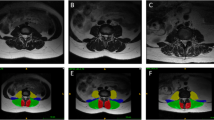

Kenneth A.Weber, Madeline Hess’s T1 axial Muscle Segmentation uses V-Net. Kenneth A.Weber’s performance is (Left DSC:0.862 ± 0.017, Right DSC: 0.871 ± 0.016) lower than Madeline Hess’s performance (DSC:0.88). This is because the elements that make up v-net are different. Table 4 compares these differences. We also compared the performance of the 3D CNN and 2D CNN. In E. O. Wesselink's study, the objective was to compare the performance between 2D convolutional neural networks (CNNs) and 3D CNNs. While 2D CNNs are designed to extract features from 2-dimensional images, 3D CNNs do so from 3-dimensional volumetric data. In this study, data augmentation techniques were applied, and the True positive rate (TPR) for right-sided muscles specifically the multifidus, erector spinae, and psoas major was compared between the two models. As indicated in Fig. 2, the 2D model demonstrated superior performance in identifying muscles when compared to the ground truth, outperforming the 3D model. The performance of the segmentation model varies depending on the presence and severity of spine pathology [19]. In Benjamin Dourthe's study, the Dice Similarity Coefficient (DSC) values for three specific Regions of Interest (ROI) were compared between healthy individuals and those with Adult Spinal Deformity (ASD). The ROIs included the vertebral body, psoas major, and multifidus erector spinae. The study uses data from five different sets to make an in-depth comparison of how well these anatomical regions are identified in both groups. Based on the analysis, the lumbar region in healthy individuals performed better in terms of ROI identification compared to those with ASD. Figure 3.